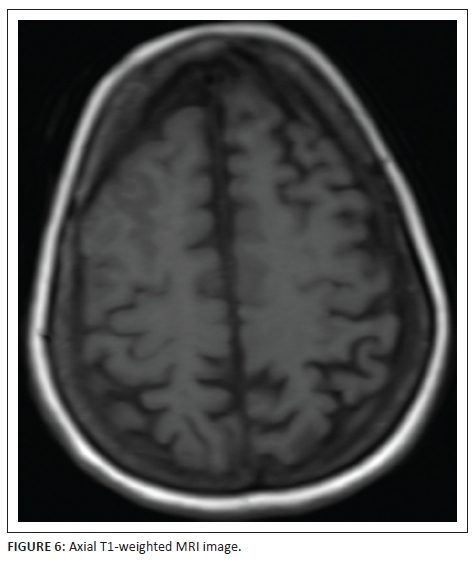

MRI study of the brain was arranged to further elucidate the cause of this unusual presentation. T2-weighted (Figure 5) and T1-weighted (Figure 6) MRI sequences confirmed the right frontal gyral swelling with effaced right middle and superior frontal sulci. Subtle gyral swelling was also observed in the parasagittal left frontal precentral region. Figure 7, a coronal FLAIR image showed, in addition to the frontal gyral swelling, an extra-axial fluid collection over the right frontal lobe convexity and in the sulci due to a sliver of subdural and subarachnoid blood respectively. A right sublenticular cyst was also incidentally noted.